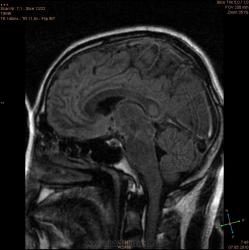

ID:56081

Болезнь Маркиафавы-Бигнами посмотри. На мой взгляд подходит.

Я заметил только 1 очаг в валике мозолистого тела. А для б-зни Маркиафавы-Бигнами более характерно несколько очагов дегенерации, в том числе и в полушариях.

По моему просто опухоль, м.б. глиобластома.

Для болезни Маркиафава-Биньями считается патогноманичным центральная дегенерация мозолистого тела.

"Болезнь Маркиафава-Биньями – Болезнь Маркиафава-Биньями (Marchiafava, Bignami)- синдром при хроническом алкоголизме: энцефалопатия в форме центрального некроза corp.callosum (иногда и других комиссур). "

Я не против, действительно м.б. "Болезнь Маркиафава-Биньями". Особенно если нет динамики.

Но диф. ряд должен быть с опухолью. И если есть негативная динамика, тогда больше похоже на то, что в моз.теле не дегенерация, а "плюс-ткань" - обьемное образование. За октябрь сканов нет?

К сожелению первое исследование проводил ни я, а моя коллега, но контроль был за мной. Уже при первом исследовании, опухолевую принадлежность можно взять под сомнение, по скольку, даже допустим возьмем глиобластому это злокачественная опухоль из глиального ряда, т.е. должен быть тумор+отек=масс-эффект, ни того и не другого нет, ко всему этому сама локализация это валик мозолистого тела, а ни гемисфера, компенсации ни должно быть ни какой, клиника должно быть молниеносной и нарастающей.

Ко всему выше перечисленному могу добавить, видимо мою коллегу сомнения гложили, она провела исследование с контрастированием и получила тот же результат.